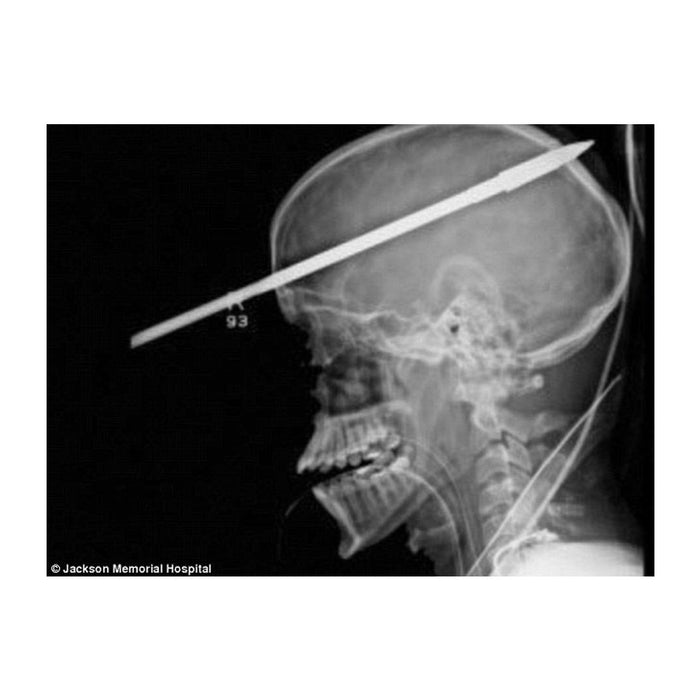

Speargun Safety - How to Handle a Speargun Safely

Why Speargun Safety is Important  Even if it's just meant for fish, spearguns are designed to kill. Speargun safety is one of the most fundamental aspects of preventing spearfishing tragedies outside of blackouts. New divers always think that their greatest risks...